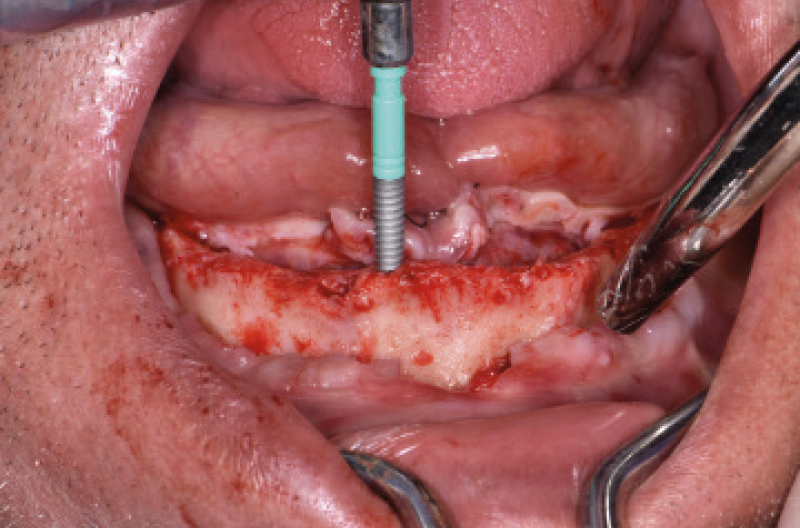

NellŌĆÖarcata inferiore ho posizionato distalmente 2 impianti Max Stability ├ś 3,75 mm L 12 e L 14 mm inclinati (ŌĆ£tiltatiŌĆØ) davanti ai forami mentonieri secondo il protocollo All-on-four, mentre nella zona sinfisaria ho inserito 2 impianti Narrow ├ś 2,9 L 12 mm (Figg. 15-20).

Fig. 18 – Inserimento degli impianti Narrow 2.9

Fig. 19 – Inserimento degli impianti distali tiltati

Fig. 20 – Vista dei 4 impianti inseriti nellŌĆÖinferiore